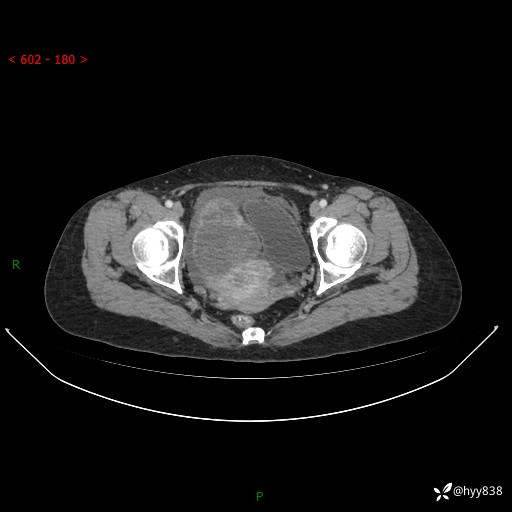

老年女性,尿频2月。超声发现盆腔囊实性占位,CT能否明确诊断---结果公布

现病史:患者绝经3-4年,期间无阴道出血及排液。患者近2月感尿频,自行口服中药治疗,症状无明显缓解。2024-4-25日于我院门诊就诊,行阴道彩超示:子宫肌瘤(大小约12*10mm,后壁),子宫右前方囊实性占位性病变(大小约126*82mm肿块声像,边界尚清,以无回声为主,可见范围约84*27mm稍高回声),内膜3mm。建议手术治疗。门诊以“卵巢囊肿”收入院。 病程中精神、食欲、睡眠可,大小便正常,体重体力无明显变化。

腹盆CT平扫

增强